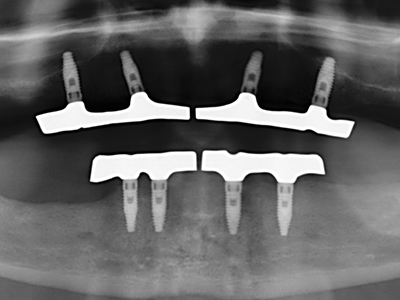

Aplicación: Obtención de hueso autógeno

En la extracción de bloques óseos la piezocirugía también presenta ventajas adicionales: Además de la alta precisión en la osteotomía que ya se ha descrito antes, se ha comprobado que el uso de los delgados insertos de sierra resulta especialmente cuidadosas con el hueso. Frente a esto, sobre todo cuando se usan las fresas de Lindemann, cabe esperar pérdidas en la extracción significativamente más altas debido al mayor grosor de la parte frontal del cabezal (Lakshmiganthan, Gokulanathan et al. 2012). La separación basal que se necesita en particular en los injertos de bloque extraídos de forma retromolar se ve facilitada mediante sierras perpendiculares especialmente previstas a tal fin, lo que permite considerar que la cirugía piezoeléctrica es un procedimiento preciso y seguro para la obtención de bloques de hueso en el área retromolar (Happe 2007) (fig. 1-12).